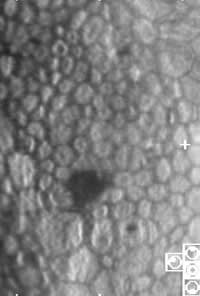

Moderately abnormal endothelial cells (cell count about 1,000 cell/mm2). |

The answer is yes. Using the Konan cell check system, either practitioner could have obtained the corneal endothelium cell count non-invasively within one minute or so. Patients who have cell counts above 2,000 cells per square millimeter have a small risk of decompensation while patients who have cell counts below 1,000 are at a much greater risk.

Although measuring the density of endothelial cells before cataract extraction isn't the present standard of care, routine use of this technology will likely identify the patients at greatest risk. These identified patients could then be given the choice of phako or ECCE.